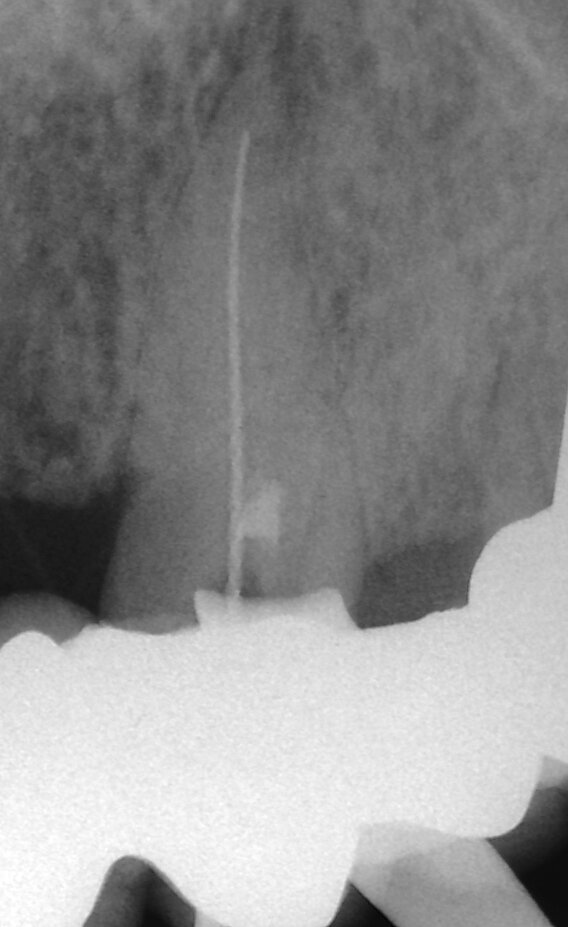

Fig. 2a: (a) Endodontically treated tooth with fistula. (b) After retreatment, the tooth showed an open apex. (c) MTA application with the MAP System and PD MTA White. Condensation of the MTA with pluggers (d) or paper points (e). (f) MTA plug. (g) Post-op radiograph showing the MTA plug and the reconstruction with a fibre post.

Fig. 2b: (a) Endodontically treated tooth with fistula. (b) After retreatment, the tooth showed an open apex. (c) MTA application with the MAP System and PD MTA White. Condensation of the MTA with pluggers (d) or paper points (e). (f) MTA plug. (g) Post-op radiograph showing the MTA plug and the reconstruction with a fibre post.

In order to prevent extrusion of root canal filling material in immature teeth with open apices, MTA is used as an apical plug. The results of many studies have shown that MTA induced apical hard-tissue formation more often and its use was associated with less inflammation than with other test materials (Figs. 2a–g).[4]